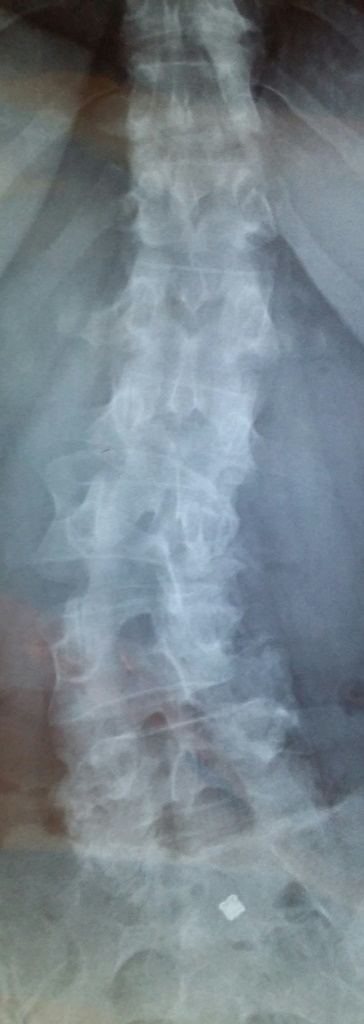

On Friday I wrote about being in pain again. I’m sharing these little ups and downs so others on this journey can see what may happen, even after diagnosis! Today is Tuesday and I have just got back from the GP. I got home from work walking stooped over. Everything from my waist down is painful – lower back, hips, knees, ankles. I lay on the bed with NO energy at all. Enough was enough and I headed to the doctor. This lovely image is my spine. Certainly not a bad case of scoliosis at all, but enough to be just an added complication given my other conditions!